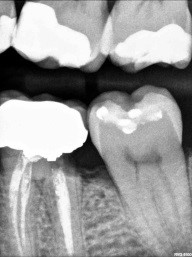

Patient 5: Tooth #18

This patient was referred from a periodontist who was going to extract #19 with socket preservation. The black and white image is deceiving, as they can be sometimes. Here, the mesial does not show a definitive lesion. It is here that the clinical examination is key. Do you examine and chase cracks? If a marginal ridge has a crack that is palpable to your explorer and is discolored, it is leaking. The photo image shows this well. The image that follows shows quite a different story than the black-and-white image. Notice the crack mid-prep is still quite prevalent.